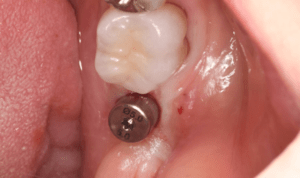

症例写真-2

- Befor

- 途中経過

- After

| 年齢 | 50代・男性 |

|---|---|

| 主訴 | 右下歯が疼く |

| 治療内容 | ・右下6番インプラント ※1:FGG(遊離歯肉移植術)とは、足りない歯ぐきを上顎から上皮を切り取り移植する外科手術 |

| 治療費 | 合計:902,000円(税込) ■内訳 |

| 治療期間 | 9ヵ月 |

| 治療方針 | 右下の当該歯は歯根破折により保存不可能と診断しました。歯周疾患も伴っていたため抜歯後に骨吸収※1が大きく起こることが予測できました。チタンメッシュ併用骨再生誘導法(GBR※2)を選択しインプラント埋入と同時に行い自然な歯槽骨のラインを再現しました。またGBRを行う際にインプラント辺縁の付着歯肉の減少が起こる為、遊離歯肉移植術(FGG※3)を行い清掃性を考慮した形態に仕上げました。 ■治療方針の解説 治療した右下の歯をレントゲンで撮影したところ根本の部分に黒く写る箇所があり「根尖性慢性周囲炎※1」と診断。また歯周病も進行していました。 ※1 骨吸収・・・歯槽骨という歯を支える骨がなくなっていくこと |

| 担当者所見 | 主訴の右下だけでなく歯茎の腫れ、発赤があり不良補綴や不良充填など他にも治療箇所が多数ありました。プラークコントロールが不良であった為まずはブラッシング指導を行いセルフケアの重要性を理解していただくところからスタートしました。 右下6番の歯はインプラント治療を行なった結果審美的にも機能的にも患者様の満足を得ることができました。骨造成と歯肉移植も行なった為インプラントを支える十分な歯周組織の獲得ができたと思っております。 |